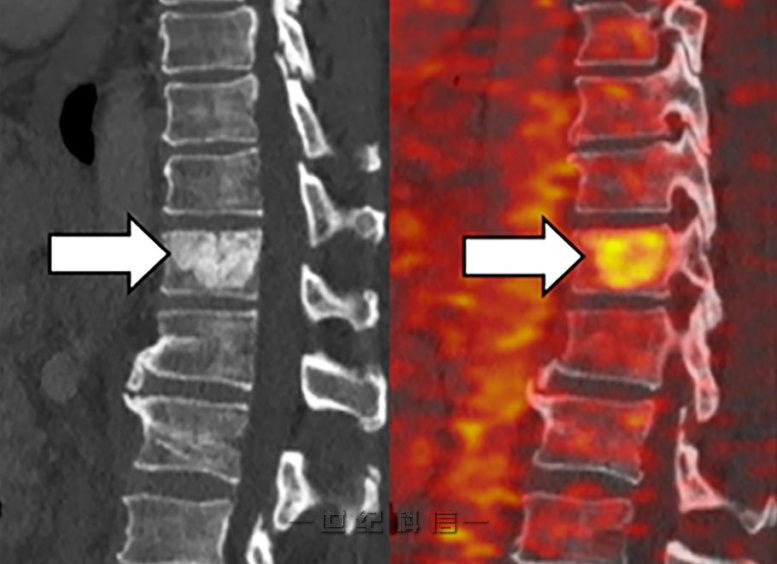

PET 成像(右)显示在胰腺导管腺癌患者的脊柱和肝脏中生长的转移性肿瘤中铁的积累。图片来源:© 2022 蒋等人。最初发表在《实验医学杂志》上。https://doi.org/10.1084/jem.20210739